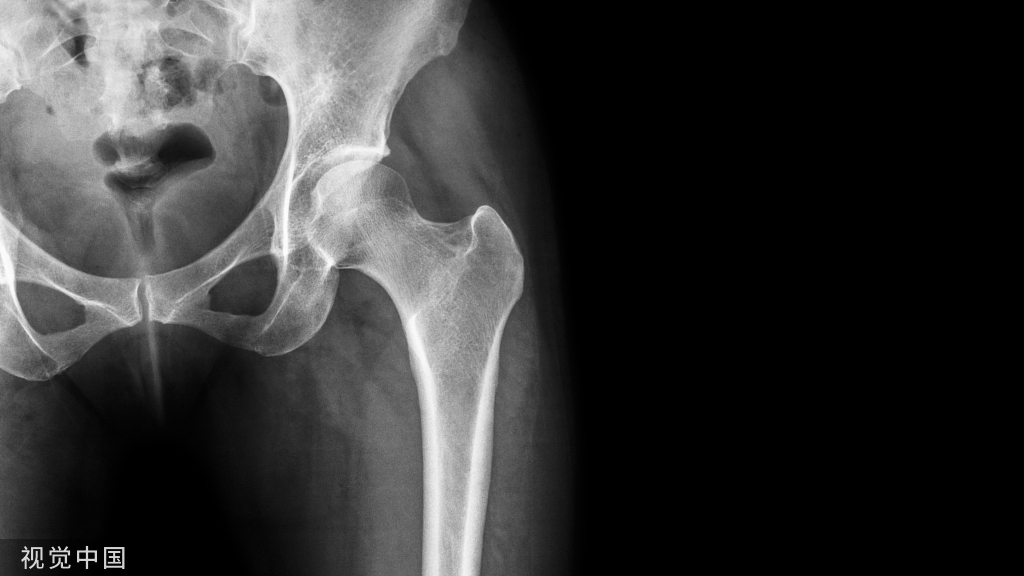

股骨骨折PFNA内固定术!